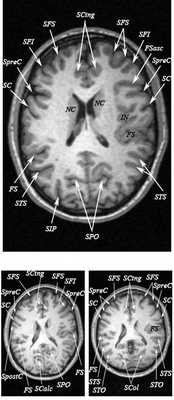

Знание анатомии мозга очень важно для правильной локализации патологических процессов. Ещё более важно оно для изучения самого мозга с помощью современных «функциональных» методов, таких как функциональная магнитно-резонансная томография (fMRI), и позитронно-эмиссионная томография. С анатомией мозга мы знакомимся ещё со студенческой скамьи и существует множество анатомических атласов, в том числе и поперечных сечений. Казалось бы, зачем ещё один? На самом деле, сравнение МРТ срезов с анатомическими приводит к множеству ошибок. Это связано как со специфическими особенностями получения МРТ изображений, так и с тем, что строение мозга очень индивидуально.

Представленная страница сайта основана на специальном изучении МРТ головного мозга здоровых лиц. Для этого изображения получали с минимальной величиной воксела (1 мм в каждом измерении), что исключало наслоения борозд. Каждая из структур прослеживалась в трёх реконструированных плоскостях путём её выделения с помощью компьютерной программы. Мы рассматривали различные анатомические варианты, что обсуждается в работе. В результате, учитывая вариабельность строения мозга, подобран условно «стандартный» мозг. Поскольку на сайте нереально представить 128 срезов в каждой из основных плоскостей, мы ограничились только каждым пятым срезом. Основные срезы в поперечной плоскости даны без наклона назад (угол 0º). Под ними для представления о изменении соотношения анатомических структур демонстрируются срезы, выполненные на тех же уровнях, но с наклонами назад -15º и -30º.

Список сокращений

Борозды

Междолевые и срединные

SC - центральная борозда

FS - Сильвиева щель (латеральная борозда)

SPO - теменно-затылочная борозда

SCing - поясная борозда

SpreC - предцентральная борозда

SFS - верхняя лобная борозда

SpostC - постцентральная борозда

SIP - внутритеменная борозда

STS - верхняя височная борозда

NC - хвостатое ядро

Поперечные (аксиальные) МРТ срезы головного мозга